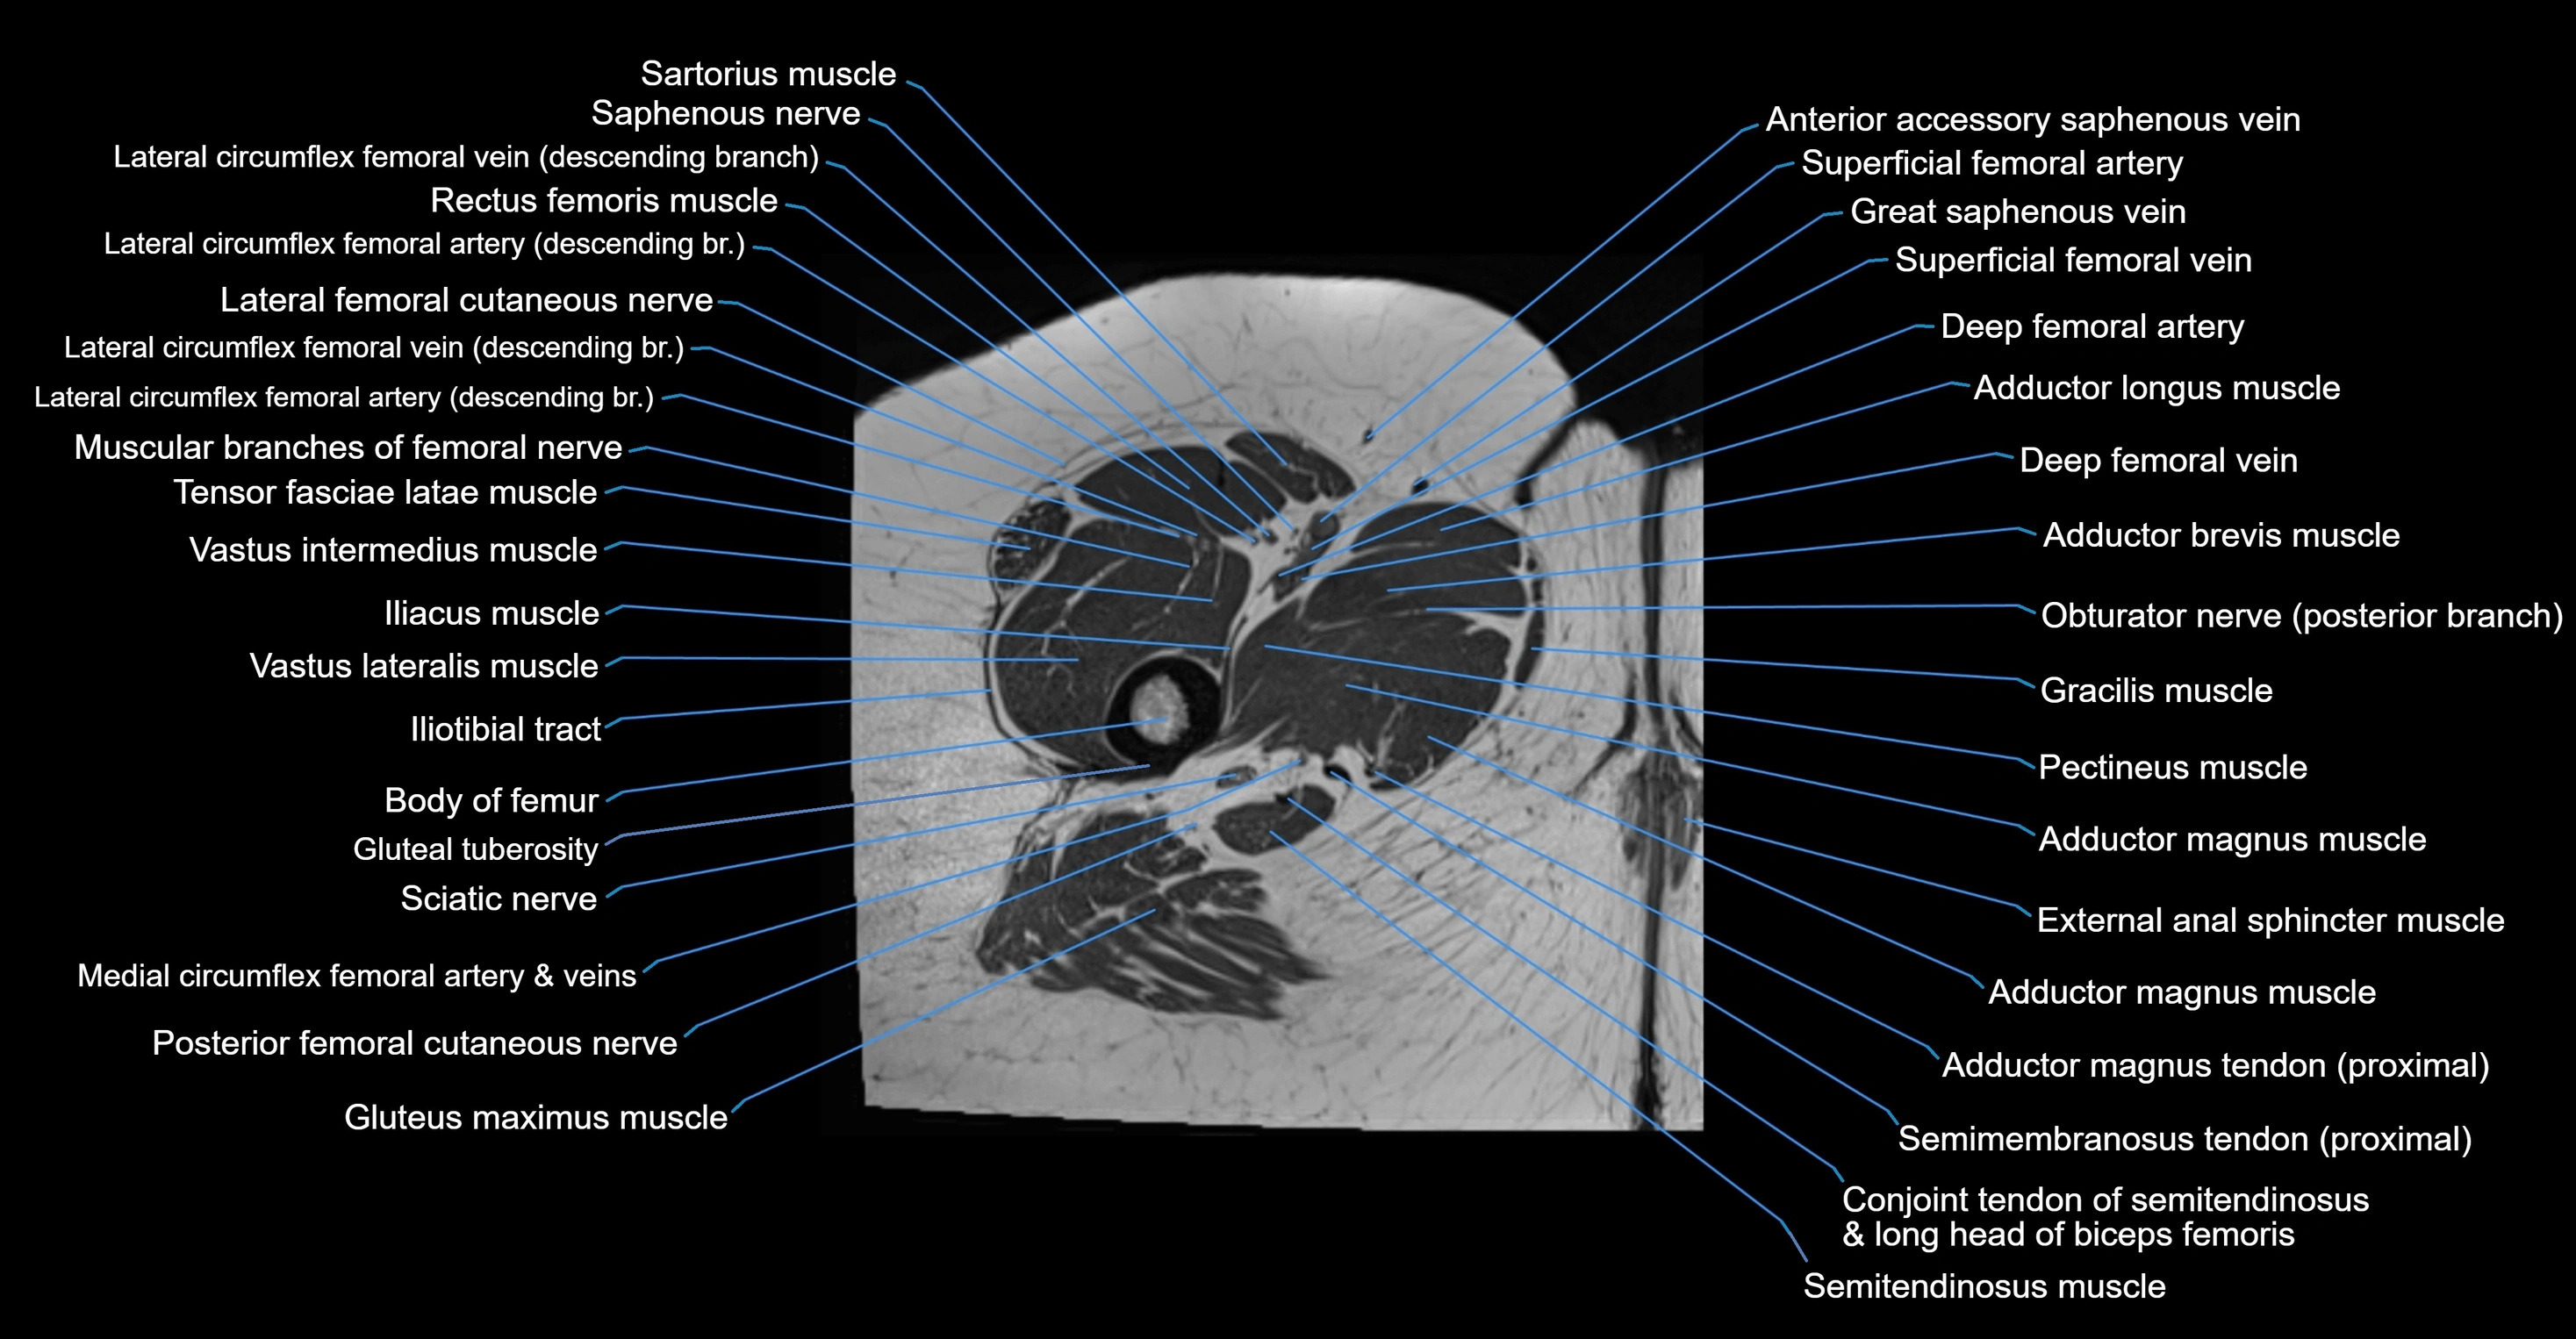

- Sartorius muscle

- Saphenous nerve

- Lateral circumflex femoral veins

- Rectus femoris muscle

- Lateral femoral cutaneous nerve

- Tensor fasciae latae muscle

- Vastus intermedius muscle

- Vastus lateralis muscle

- Iliotibial tract

- Body of femur

- Gluteal tuberosity

- Posterior femoral cutaneous nerve

- Gluteus maximus muscle

- Gracilis muscle

- Pectineus muscle

- Adductor longus muscle

- Adductor brevis muscle

- Adductor magnus muscle

- Deep femoral artery (profunda femoris)

- Deep femoral vein (profunda femoris vein)

- Superficial femoral artery

- great saphenous vein

- Conjoint tendon of biceps femoris & semitendinosus

- Semimembranosus tendon (proximal)